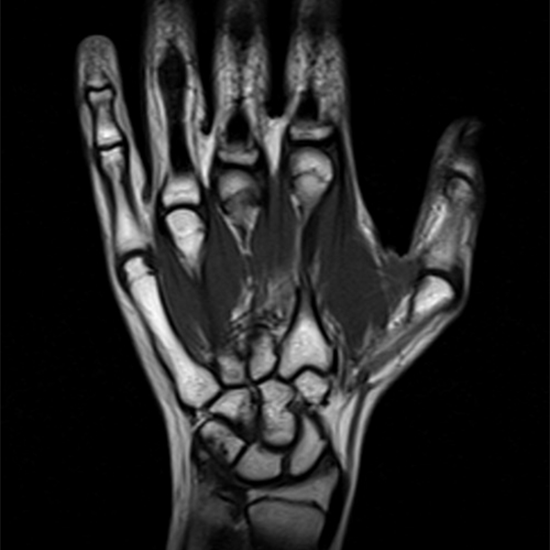

The left-hand MRI visualises its bones and joints. Checking for aberrant growths, abnormalities, and lesions in soft tissue. It identifies soft-tissue, blood vascular, or bone diseases. Hand MRIs are excellent for detecting fractures. Age-related wrist bone alterations or hand joint dislocations are also found.